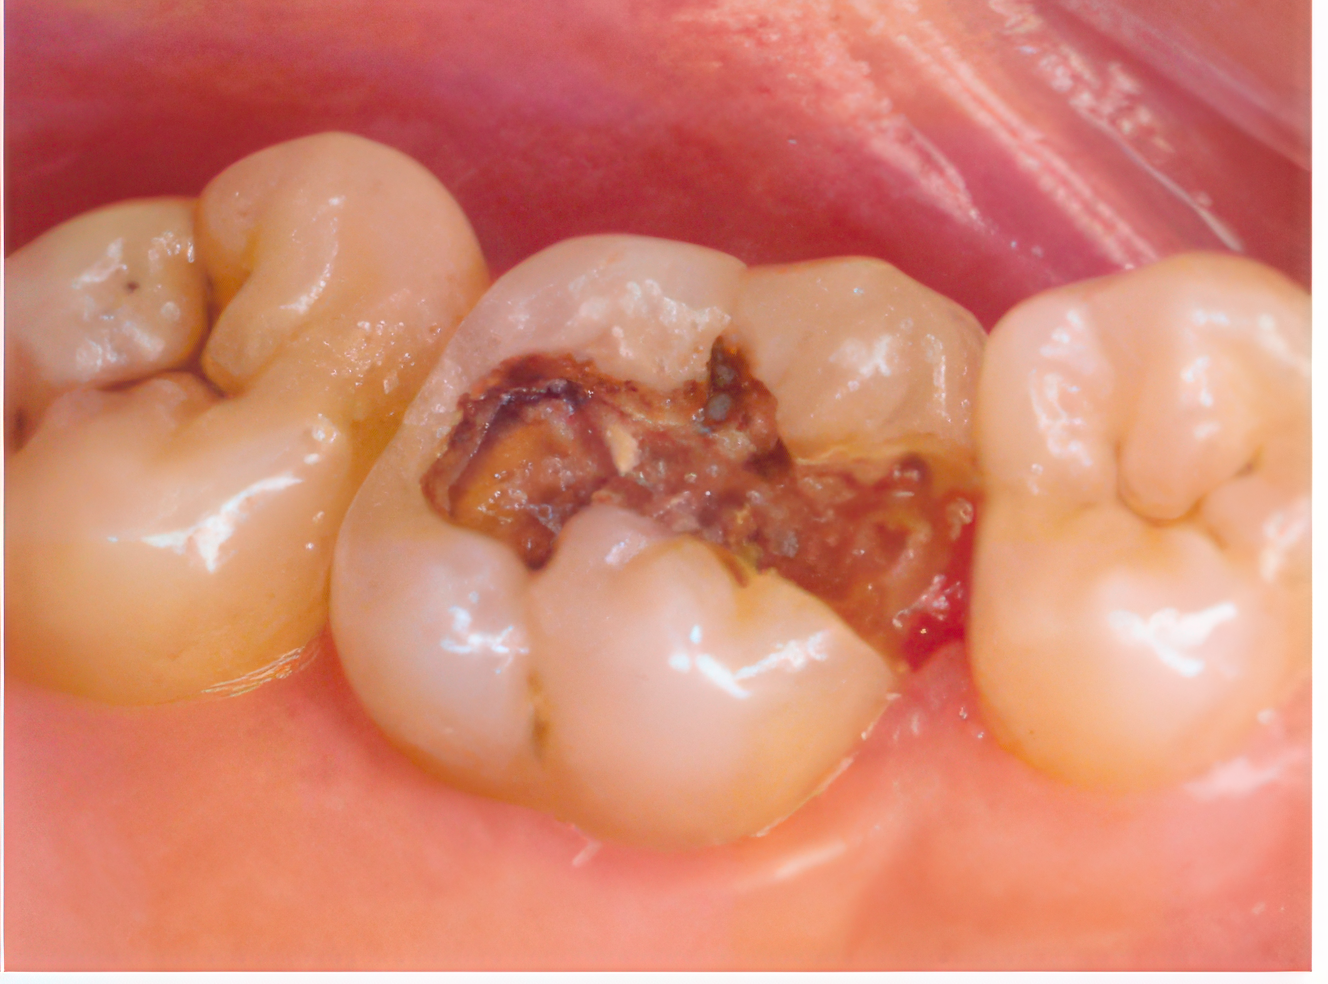

虫歯治療は進行度に応じて治療します

機能性や審美性も考慮します

歯は表層からエナメル質、象牙質、歯髄の三層構造から成り、歯根膜を介して歯槽骨に支持されています。適切なブラッシングが行われない場合、歯表面に残った磨き残しがプラークとなり、その中の細菌が虫歯や歯周病を引き起こします。虫歯の原因菌であるストレプトコッカス・ミュータンスは糖分を栄養源として酸を生成し、この酸が歯のエナメル質を溶かして虫歯を発生させます。虫歯の進行には、摂取する糖分の量、歯質の強度、そして放置する時間の長さが影響します。

前歯の虫歯治療では、虫歯が小さい場合には歯に近い色のレジン(樹脂)で充填を行います。虫歯が広範囲に及ぶ場合は、歯を覆うクラウン(被せ物)による処置を行いますが、審美面に配慮し、見た目に金属が露出しないように工夫されています。奥歯の虫歯に対しては、接触面に虫歯が発生した場合、虫歯部分を除去してから型を取り、適合の良い金属で詰める治療を行います。噛み合わせ面に小規模な虫歯が限局している場合には、レジン充填を用いることも可能です。

これらの治療法は、それぞれの歯の位置や虫歯の進行状態、また審美的な要素を考慮して選択され、機能と見た目の両面において自然な仕上がりを目指しています。